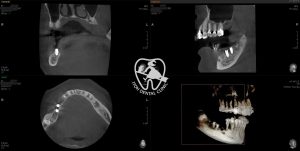

インプラントは人工の歯根を骨に埋めるために骨にドリリングを行う治療となりますので当院では血管や神経等の重要な器官を傷つけないように歯科用CTによる三次元診断・シミュレーションおよびサージカルガイド(ドリリング時に深くなりすぎたり大きく傾斜してしまわないようにする道具)を用いて安全に配慮したインプラント埋入を行っております

この患者さんの場合、最初の計画では5番と7番にインプラントを埋入し6番をポンティックにするインプラントブリッジとするデザインの予定でしたが、5番抜歯時に残根が骨に癒着しまっており完全に抜歯しきる際に骨を削らざるを得なく骨欠損ができてしまいました

CT診断により6番相当部位に豊富に骨があることは分かっておりましたので治療期間短縮を図るため6番7番にインプラントを埋入し、5番を延長ポンティックとするデザインに了承を得て変更いたしました